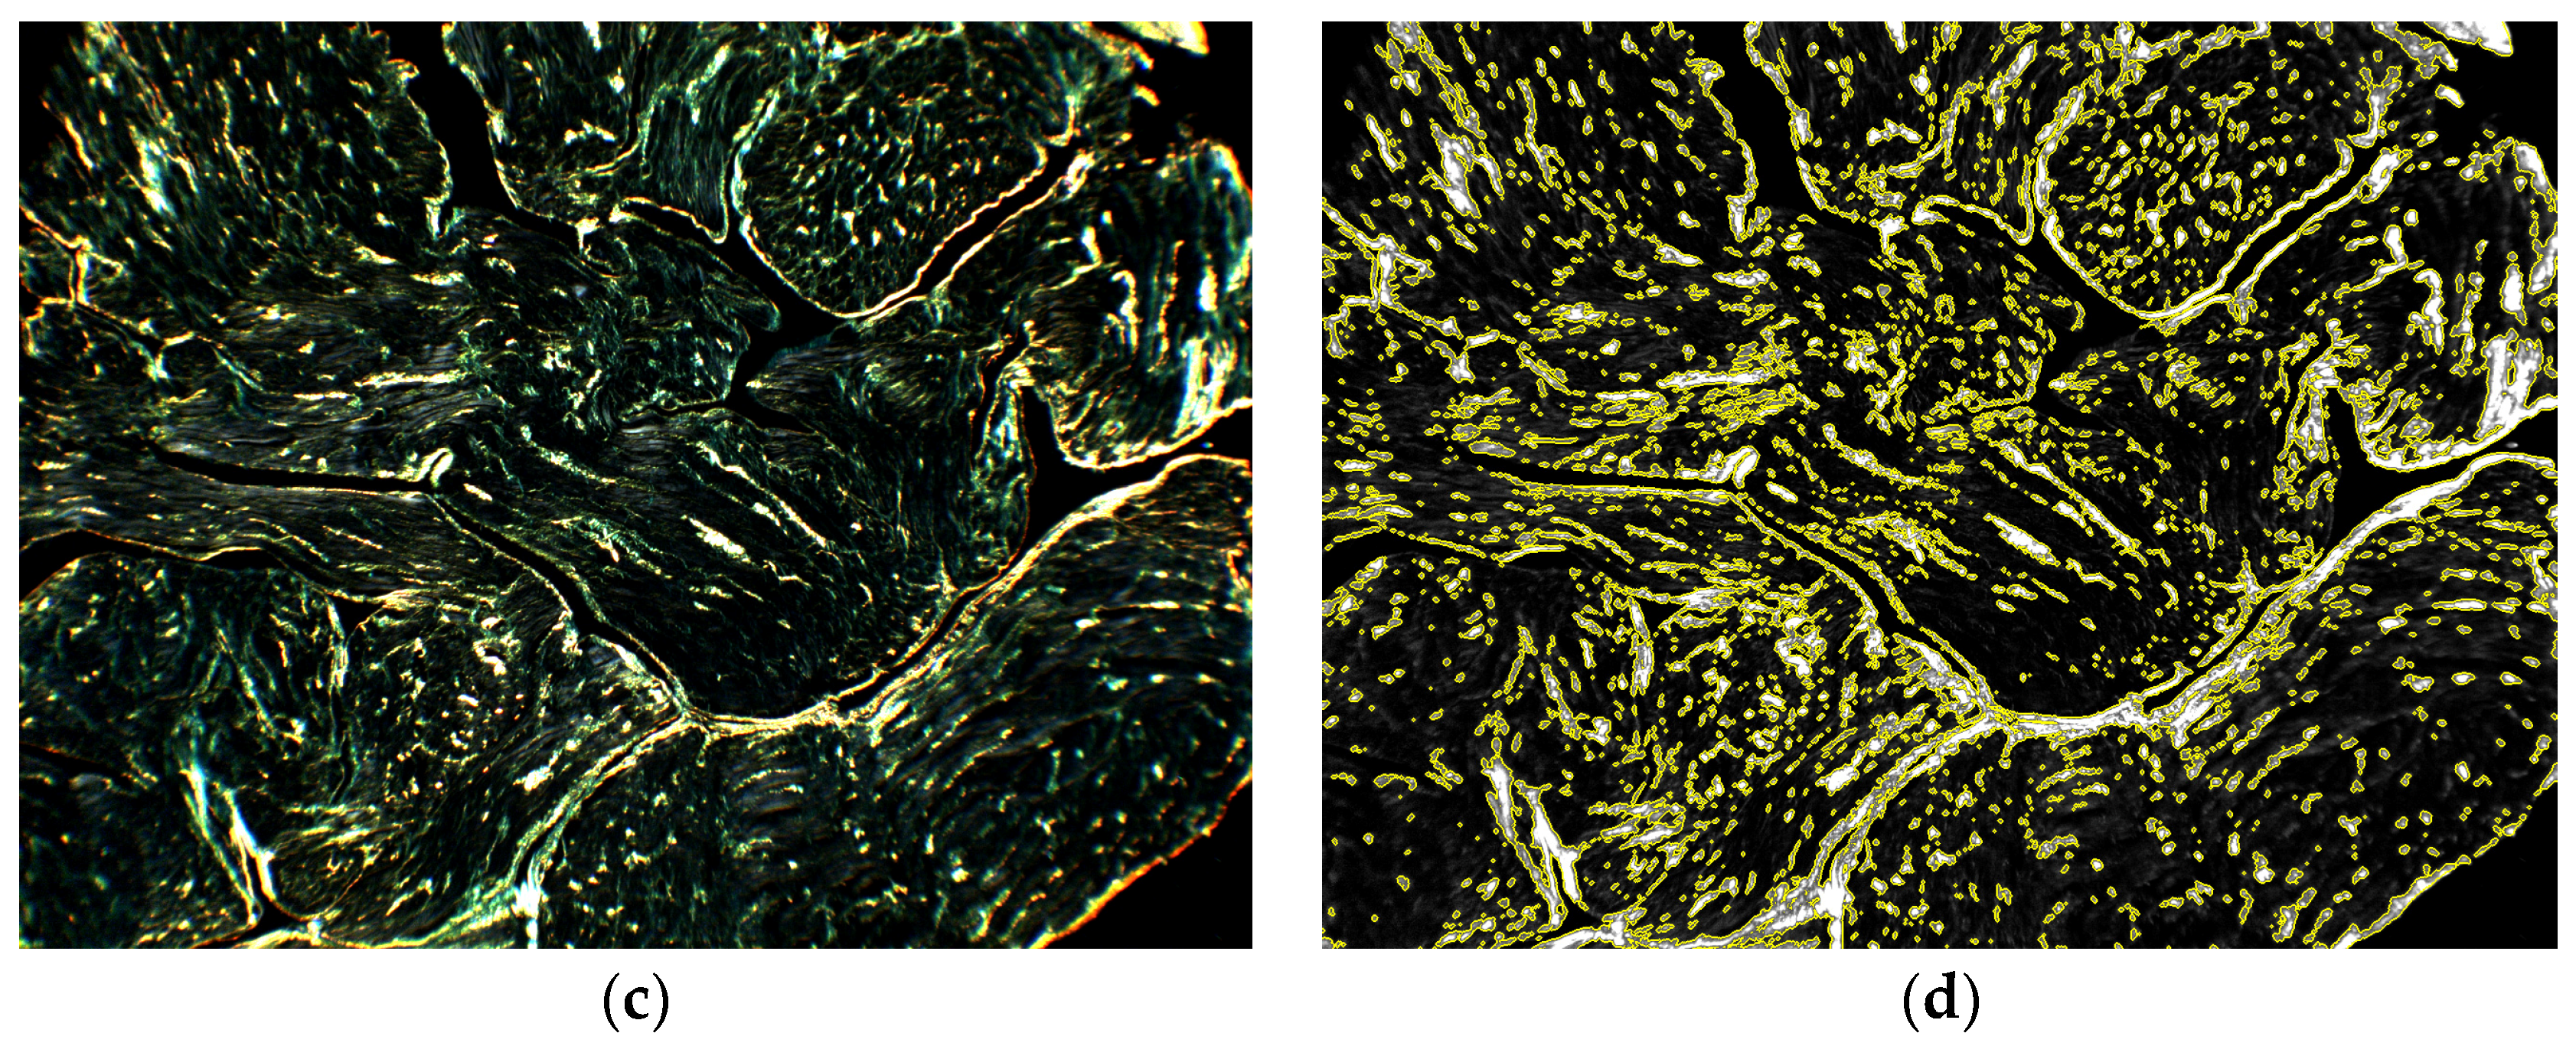

A representative example of the birefringence analysis is shown in Figure 4 for the same section shown in Figure 3. The intensity of the original dark-field image A c i (Figure 4a) is affected by source illumination, acquisition exposure, sample transmittance, and a nonzero transmittance T c of the crossed polarizers. These factors create a background illumination, which could interfere with birefringence detection. The corrections applied through the processing pipeline up to Equation (13) isolated the birefringence signal produced by the sample (Figure 4b), reducing the aforementioned artifacts. The subsequent application of Equation (14) compensated for the effects of section thickness variability. As shown in Figure 4c, the signal was normalized to unitary average optical thickness, producing the RGB image S b i r i , which was representative of collagen density in the tissue. The RGB collagen signal was transformed into a greyscale image S c o l i (Figure 4d), suitable for segmentation of the high-collagen tissue in the sample by thresholding according to t c o l . The collagen segmentation mask m a s k c o l i produced for the threshold t c o l = 0.152 (see next Section) is highlighted in yellow in Figure 4d. Combining the collagen mask with the tissue mask m a s k t i s i , the collagen fraction c i of the sample was computed according to Equation (17), giving a value of 14.3% for the shown example.

Figure 4. Birefringence processing and collagen segmentation: (a) Original dark-field image A c i (windowed 0–32,768); (b) RGB birefringence signal in Equation (13) obtained after correcting for nonuniform illumination, transmittance of the sample, and crossed transmittance T c of the polarizers (windowed 0–0.05); (c) RGB birefringence signal S b i r i , obtained according to Equation (14) by normalizing the original optical thickness of 0.22 to unitary optical thickness (windowed 0–0.5); (d) Greyscale collagen signal S c o l i from Equation (15) (windowed 0–0.5). The collagen mask m a s k c o l i was obtained for a collagen threshold t c o l = 0.152. The high-collagen area, contoured in yellow, comprised a collagen fraction c i = 14.4%.